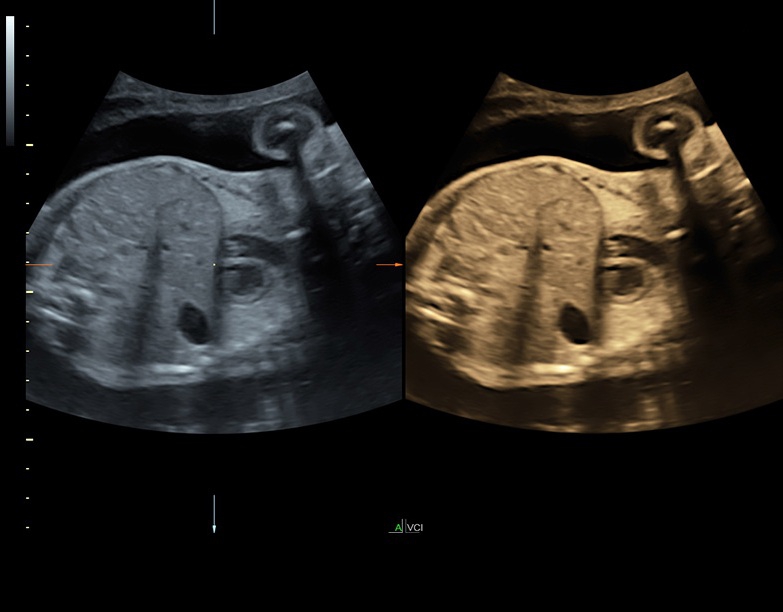

Аппарат Voluson S8 базируется на надежной платформе VCA, которая имеет множество положительных отзывов. Она обладает высококонтрастной технологией объемной реконструкции, обеспечивая качественное воспроизведение изображений. Информация выводится на широкоформатный цветной монитор размером 23 дюйма для убедительной демонстрации плода будущим родителям и облегчения работы врача.

• Высокое качество изображений: Voluson S8 обеспечивает высококачественные изображения, позволяющие детально оценить состояние плода и обнаружить возможные патологии.

• Сложные инструменты для оценки качества плода: Сканер оснащен инновационными инструментами, позволяющими проводить детальную оценку состояния плода, включая его сердечную деятельность, анатомию и кровоток.

• Технология SonoRenderlive: Эта технология облегчает получение 3D/4D изображений путем автоматического изменения положения плоскости визуализации в зависимости от движений плода. Она позволяет получить реалистичные и объемные изображения, что полезно для демонстрации плода будущим родителям и для дополнительного анализа.